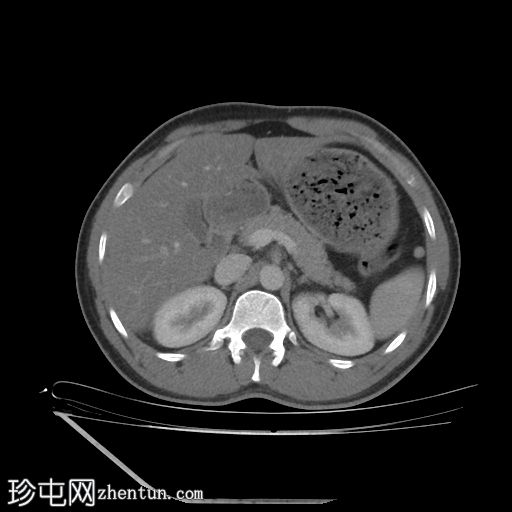

轴位增强扫描

门静脉期

4.jpg

双侧肾脏集合系统重复,分为上极和下极两部分。右侧输尿管在中段汇合,而左侧输尿管在进入膀胱前仍部分分离,符合双侧部分输尿管重复畸形(双分输尿管)。

双侧重复肾盂输尿管系统,上下极部分明显。右侧重复的输尿管在中段汇合,而左侧输尿管在进入膀胱前仍部分分离,符合双侧部分输尿管重复畸形(双分输尿管)。双肾大小、位置、轮廓和实质厚度均正常,造影剂浓度和排泄功能正常。未见肾结石、肾积水或局灶性肾脏病变。

其他偶然发现包括II级肝脂肪变性、胃脾区可见一小副脾、双侧L5椎弓崩裂伴L5相对于S1的I级滑脱。